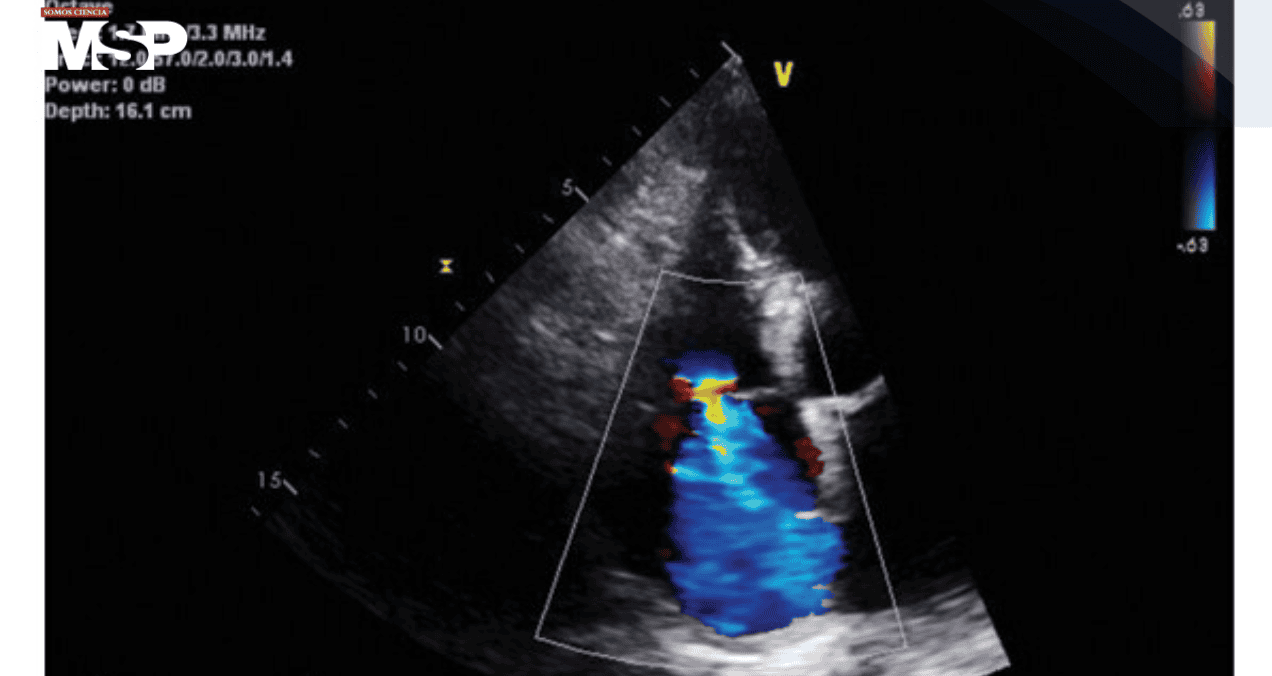

Los estudios iniciales descartaron patología intracraneal aguda, pero el ecocardiograma reveló hipertensión pulmonar, regurgitación tricuspídea severa, dilatación de la aurícula derecha y fracción de eyección preservada. En la piel se observaban petequias bilaterales en extremidades inferiores, junto a los signos marcados de malnutrición.

Ante la combinación de síntomas cardiopulmonares sin etiología clara, un cuadro neuropsiquiátrico agudo y signos dermatológicos compatibles, se consideró la posibilidad de escorbuto.

Los niveles séricos de vitamina C confirmaron la sospecha al encontrarse indetectables. La paciente inició suplementación intravenosa de ácido ascórbico, experimentando una mejoría progresiva de la disnea y del estado mental.

Tras ocho días de hospitalización fue dada de alta, aunque se perdió el seguimiento ambulatorio, lo que impidió demostrar ecocardiográficamente si la hipertensión pulmonar había revertido con la terapia.

En la primera paciente, la profunda deficiencia de vitamina C ofrecía una explicación plausible para la hipertensión pulmonar en ausencia de otras causas estructurales o autoinmunes.